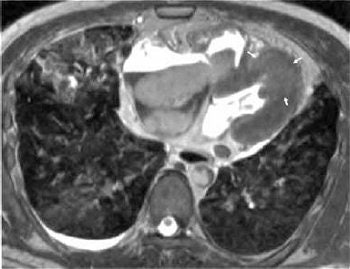

![]() |

| Sixty-seven-year-old man with transmural myocardial infarction after occlusion of circumflex artery. Nine MR images, acquired with inversion-recovery true fast imaging with steady-state precession (trueFISP) during a single breath-hold, reveal transmural infarction (arrow) as hyperenhanced region in inferolateral segments. Huber A, Schoenberg S, Spannagl B, Rieber J, Erhard I, Klauss V, Maximilian F, Reiser M, "Single-Shot Inversion Recovery TrueFISP for Assessment of Myocardial Infarction" (AJR 2006; 186:627-633). |

For this prospective study, 43 patients with MI were enrolled. They underwent MR imaging on a 1.5-tesla scanner with eight channels and a dedicated 12-element phased-array body coil (Magnetom Sonata, Siemens Medical Solutions, Malvern, PA). Ten minutes after gadodiamide was injected (0.2 mmol/kg), a segmented inversion-recovery cine trueFISP pulse sequence was done, at a midventricular short-axis location, to establish a T1 scout. Immediately after that, the single-shot 2D inversion recovery was performed in a single breath-hold. Seventeen cardiac cycles were necessary to image nine slices. A segmented inversion-recovery turboFLASH sequence was used to cover the entire left ventricle in the short-axis view.

According to the results, 18 infarctions were located in the anteroseptal segments, 16 in the inferoseptal segments, and nine in the inferolateral segments. The trueFISP sequence showed a lower CNR than turboFLASH for viable and nonviable myocardium, the authors stated.